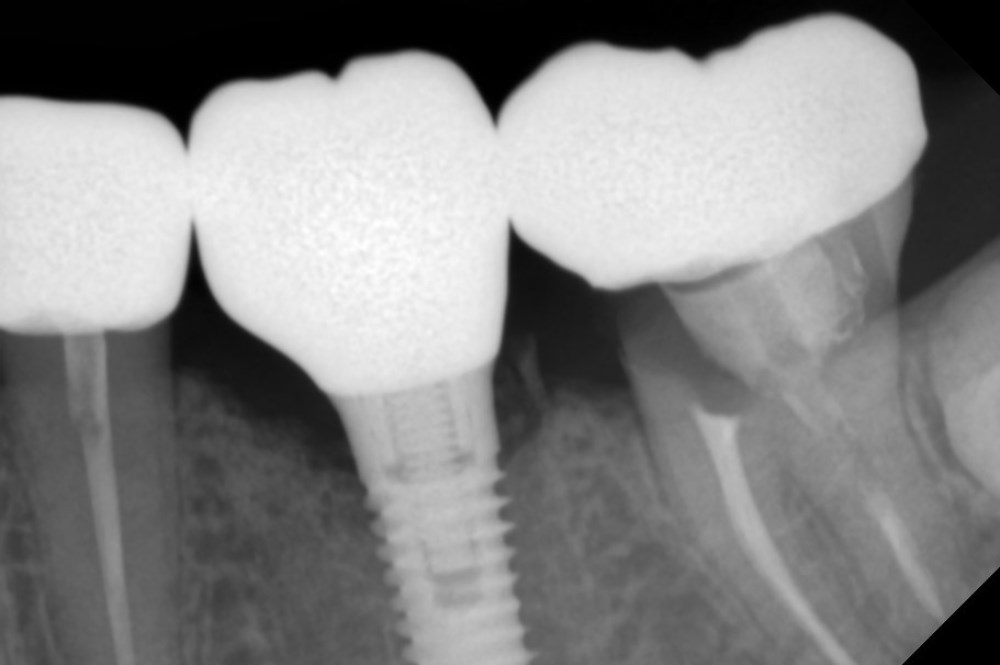

Имплантация жевательных зубов,

это самая востребованная операция.

Анна Анатольевна Кушнарева

хирург - имплантолог

рентген имплантатоы

фото коронок